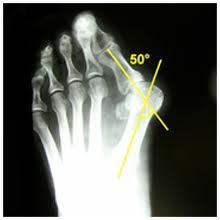

Il reparto di ortopedia dell’ospedale di Foligno è all’avanguardia nella chirurgia dell’alluce valgo: una nuova tecnica chirurgica, infatti, viene utilizzata dal dottor Stefano Ferranti – chirurgo ortopedico della struttura complessa di ortopedia e traumatologia – diretta dal dottor Carlo Farneti, per la correzione dell’alluce valgo. La metodica chirurgica denominata M.I.C.A. consiste in una procedura mini invasiva, che permette la correzione dell’alluce valgo senza ricorrere alla tradizionale chirurgia aperta, utilizzando mini frese motorizzate inserite attraverso piccoli fori di accesso sulla pelle. Previsto l’utilizzo di viti per garantire maggiore stabilità delle osteotomie eseguite per la correzione. L’intervento avviene in regime di day surgery, con un'anestesia loco regionale – blocco del piede – e permette la dimissione dei pazienti lo stesso giorno dell’intervento con la possibilità di deambulare subito con una speciale scarpa ortopedica. Il dottor Stefano Ferranti, dopo aver partecipato al corso di chirurgia sulla suddetta tecnica presso il Sussex Orthopaedic Treatment dell’Università di Brigthon in Inghilterra, è stato anche il promotore della giornata di istruzione chirurgica che si è svolta presso il presidio ospedaliero. Grazie alla nuova tecnica e alla professionalità del reparto ortopedico del San Giovanni Battista, l’Ospedale di Foligno è un centro di riferimento nazionale per molte pazienti che devono affrontare l’operazione per correggere l’alluce valgo.